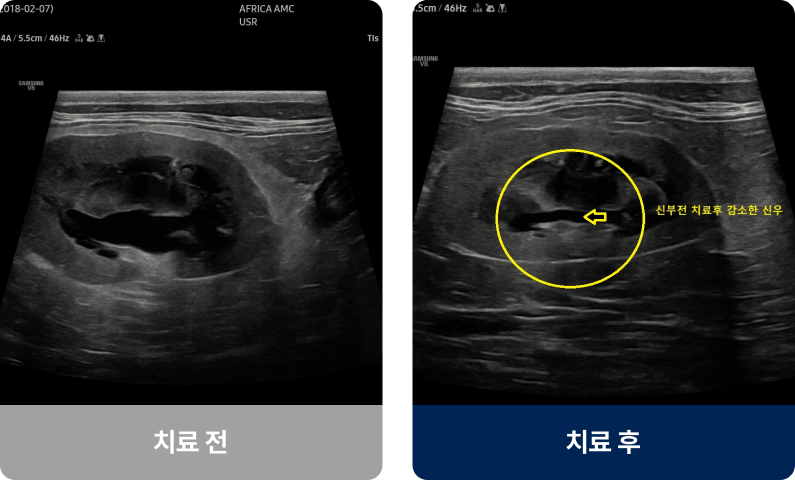

노화나 탈수, 고혈압, 유전적 요인 등으로 신장의 여과 기능이 서서히 저하되는 질환입니다. 주로 7세 이상 노령견이나 고양이에게 많이 발생하며, 물을 많이 마시고 소변량이 늘거나 식욕이 감소하는 증상을 보입니다. 진행되면 구토, 체중 감소, 입 냄새, 무기력 등 전신적인 증상으로 이어질 수 있습니다.

내과적 치료법(비수술적 치료)

손상된 신장을 되살리는 것은 어렵지만,

남은 기능을 최대한 유지하고 증상을 완화하는 치료입니다.